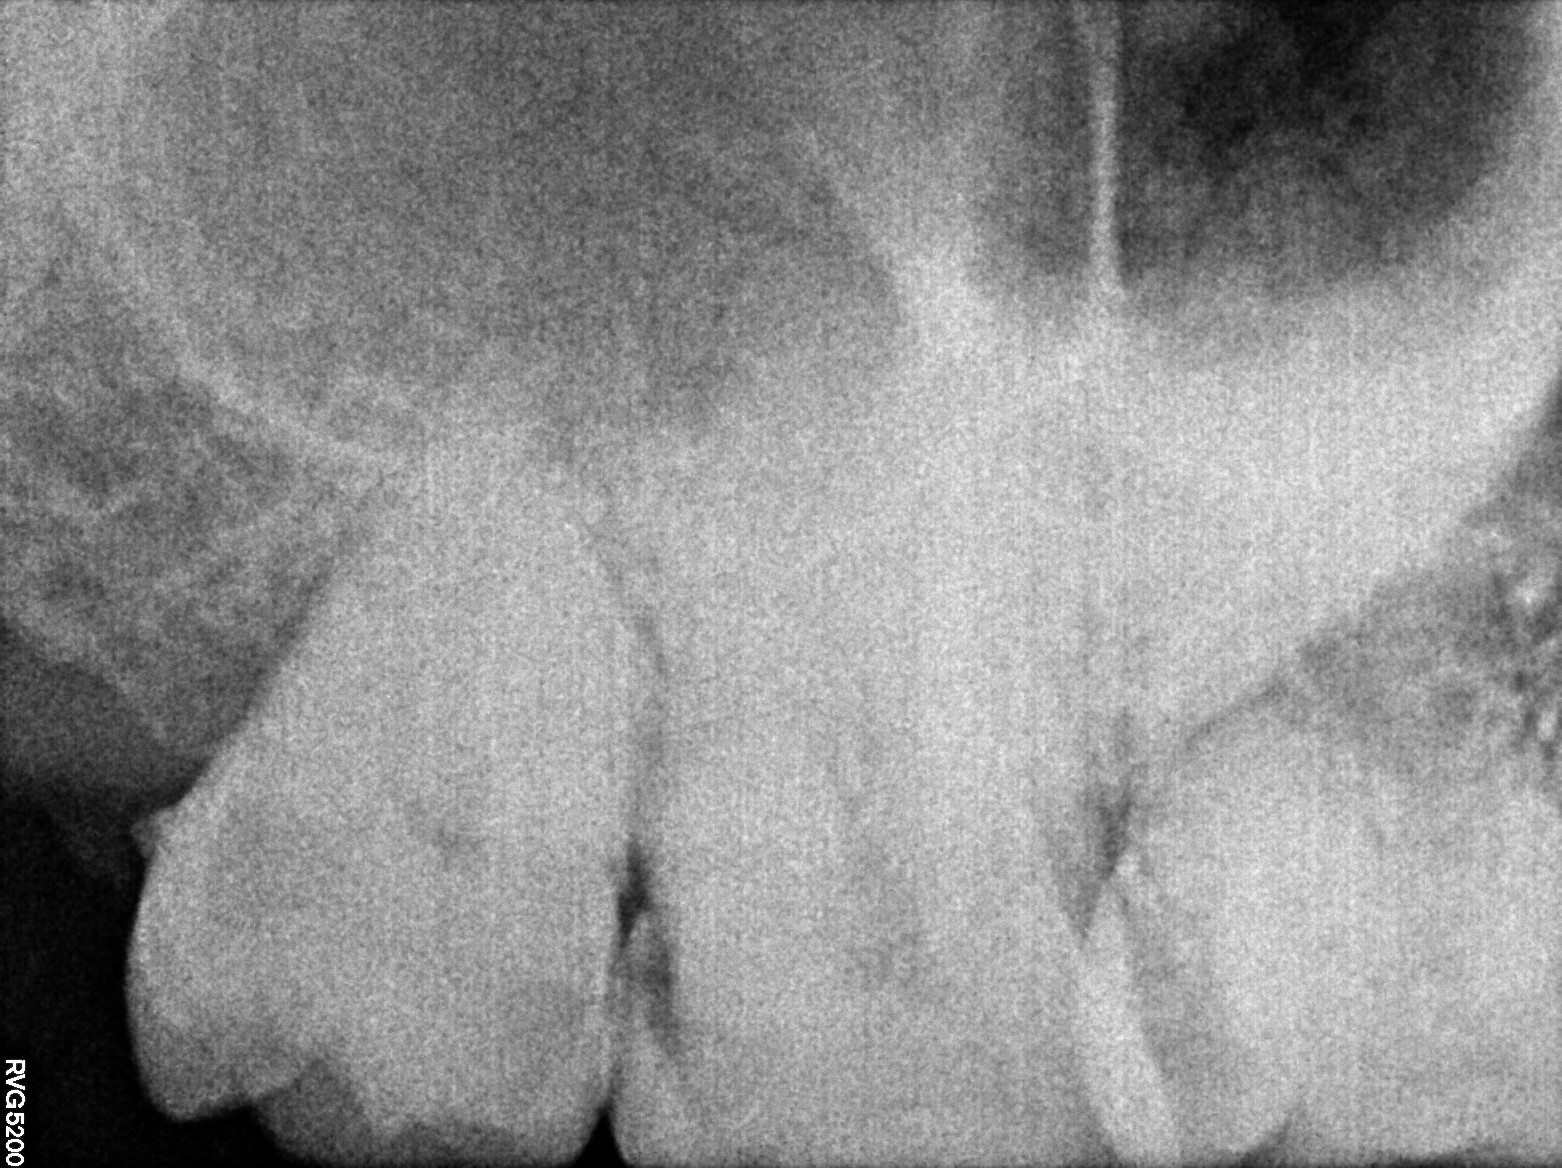

Dental Radiographs FHIR: DocumentReference · LOINC 24641-7

xray_1772727889_1.jpg

24641-7

xray_1772727889_0.jpg